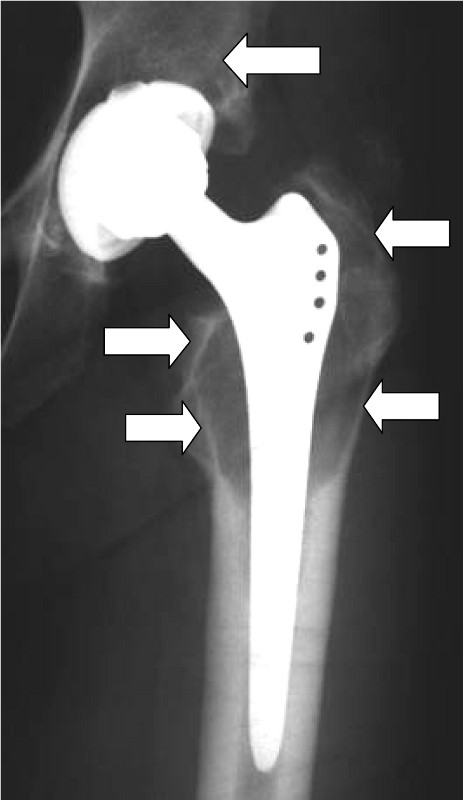

Nickel or chromium are contained in almost all orthopedic implants made of stainless steel or cobalt-chromium alloys. Sensitization of the immune system to metal ions is a prerequisite for the development of implant intolerance. An important factor in the development of intolerance is the amount of particle formation (metal ions), as well as the release and distribution of metal ions. Correspondingly, corrosion and wear behavior of the implant material have a significant influence on the development of a hypersensitivity reaction. This usually occurs after a symptom-free interval. Activation of various cells of the immune system finally leads to premature loss of the prosthesis.

Although statistically only a small proportion of patients develop such hypersensitivity (the figures are less than 1% or between 1 and 4%, depending on the author), we attach great importance to the diagnosis and treatment of hypersensitivity reactions to prostheses in our hospital. If there is a proven allergy to prosthesis components, patients can be fitted with special prostheses made of titanium (hip) or implant coatings (knee). All-ceramic prostheses are currently still undergoing clinical trials. Before considering an implant allergy, however, other causes of the complaints, such as infections, mechanical problems or malpositioning, should be ruled out.

Beschichtete KnietotalendoprotheseDiffuse Lymphozyteninfiltration in der GelenkkapselOsteolyse um einen Prothesenschaft (Pfeile)